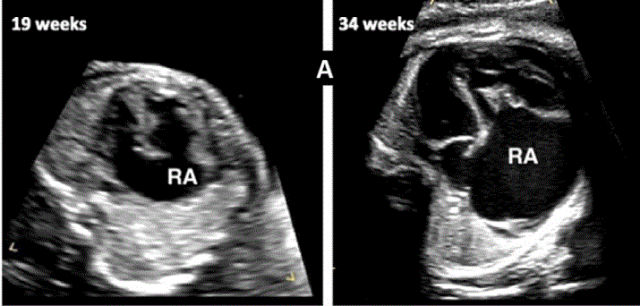

图27进展性主动脉狭窄。一例23周胎儿的严重主动脉狭窄,伴有扩张和低动力性左心室(LV)伴心内膜弹性纤维变性。(A) 彩色多普勒显示,主动脉瓣(箭头)开始出现花彩血流(左),频谱多普勒显示阶差为 25 毫米汞柱(右(B) 二尖瓣(MV)流入是单相的,持续时间短(左),二尖瓣反流提示左心室收缩压高(46毫米汞柱压力梯度加左心房压力;右图)。(C)存在逆行主动脉弓流(红色,左)和左至右心房流(红色、右)是预测由于通过左心的流量减少而在妊娠期间发展的进行性左心发育不全的额外发现。(D)LV逐渐变为球状,长度缩短,到36周时不再形成心尖。

图29胎儿Ebstein异常和TV发育不良。(A)在该胎儿中,严重的三尖瓣反流与进行性心脏增大有关,尤其是右心房(RA)扩张,如这些在19周和34周时的系列图像所示,并且可能与心力衰竭/水肿的演变有关。(B-D)四腔切面中胎儿严重Ebstein异常显示严重心脏扩大的图像。(C)从矢状切面可见广泛的三尖瓣反流(箭头),由于室间隔瓣叶移位,反流起源于TV瓣环下方,甚至向 RV 流出道射流。彩色多普勒和 CW 多普勒显示也有连续的肺动脉反流。(D) 后一项发现表明,右心室无法产生足够的压力来打开肺动脉瓣